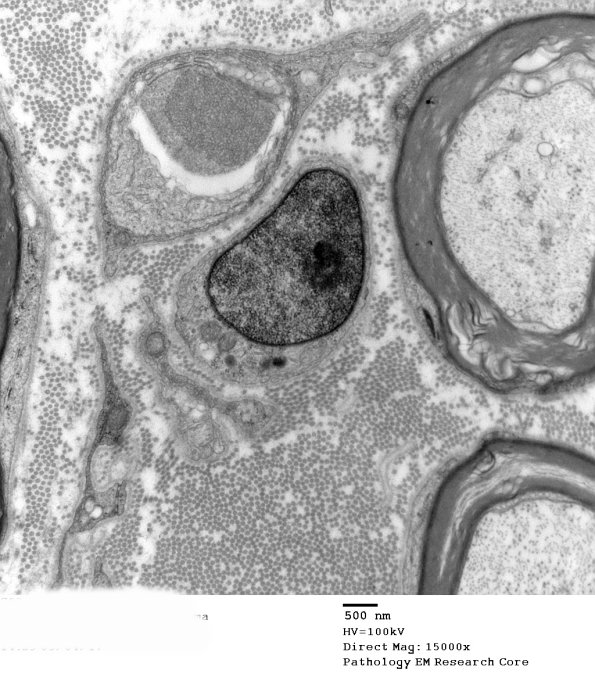

There does appear to be unmyelinated axon loss in this nerve and, surprisingly, there are numerous dystrophic axons with compact tubulovesicular elements. (electron micrographs)